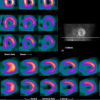

Study Reveals Low Adoption of IAEA Recommendations for Reduced Nuclear Cardiology Radiation Exposure

May 12, 2017 — A study in 65 countries has revealed low adoption of International Atomic Energy Agency (IAEA)…

May 11, 2017 — A large nuclear cardiology laboratory in Missouri has slashed its average radiation dose by 60 percent…